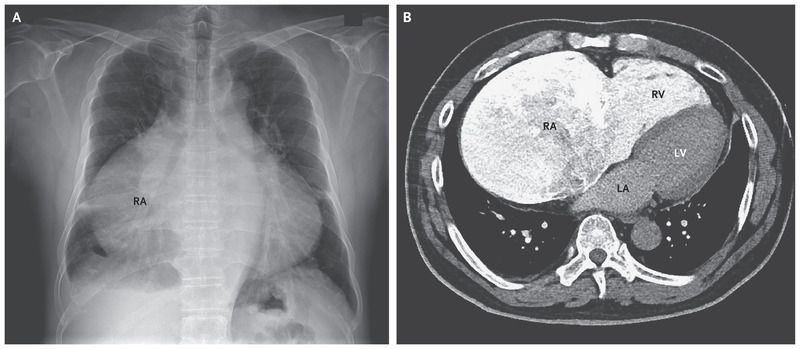

A 57-year-old man presented to the emergency department with peripheral edema. Findings on physical examination were consistent with atrial fibrillation, tricuspid regurgitation, and heart failure on the right side. A radiograph of the chest showed a high cardiothoracic ratio of 0.82 and a very large right atrium (RA; Panel A). Transthoracic echocardiography (Fig. S1 in the Supplementary Appendix, cardiac computed tomography (Panel B, and Figs. S2 and S3 in the Supplementary Appendix), and cardiac magnetic resonance imaging (Fig. S4 in the Supplementary Appendix) revealed a giant right atrium, a dilated right ventricle (RV) with preserved systolic function, grade 4/4 functional tricuspid regurgitation, high-normal right-ventricular systolic pressure, and normal size and function of the left ventricle (LV). LA denotes left atrium. No shunt was identified. Medical therapy, including oral anticoagulation for atrial fibrillation, was initiated, with good response, and the patient’s condition remained stable 1 year after presentation. Giant right atrium is a rare congenital condition that causes functional tricuspid regurgitation and heart failure on the right side. It is usually diagnosed in childhood. Other, more common causes of right atrial enlargement such as pulmonary hypertension, tricuspid-valve stenosis, and Ebstein’s anomaly were not identified in our patient.